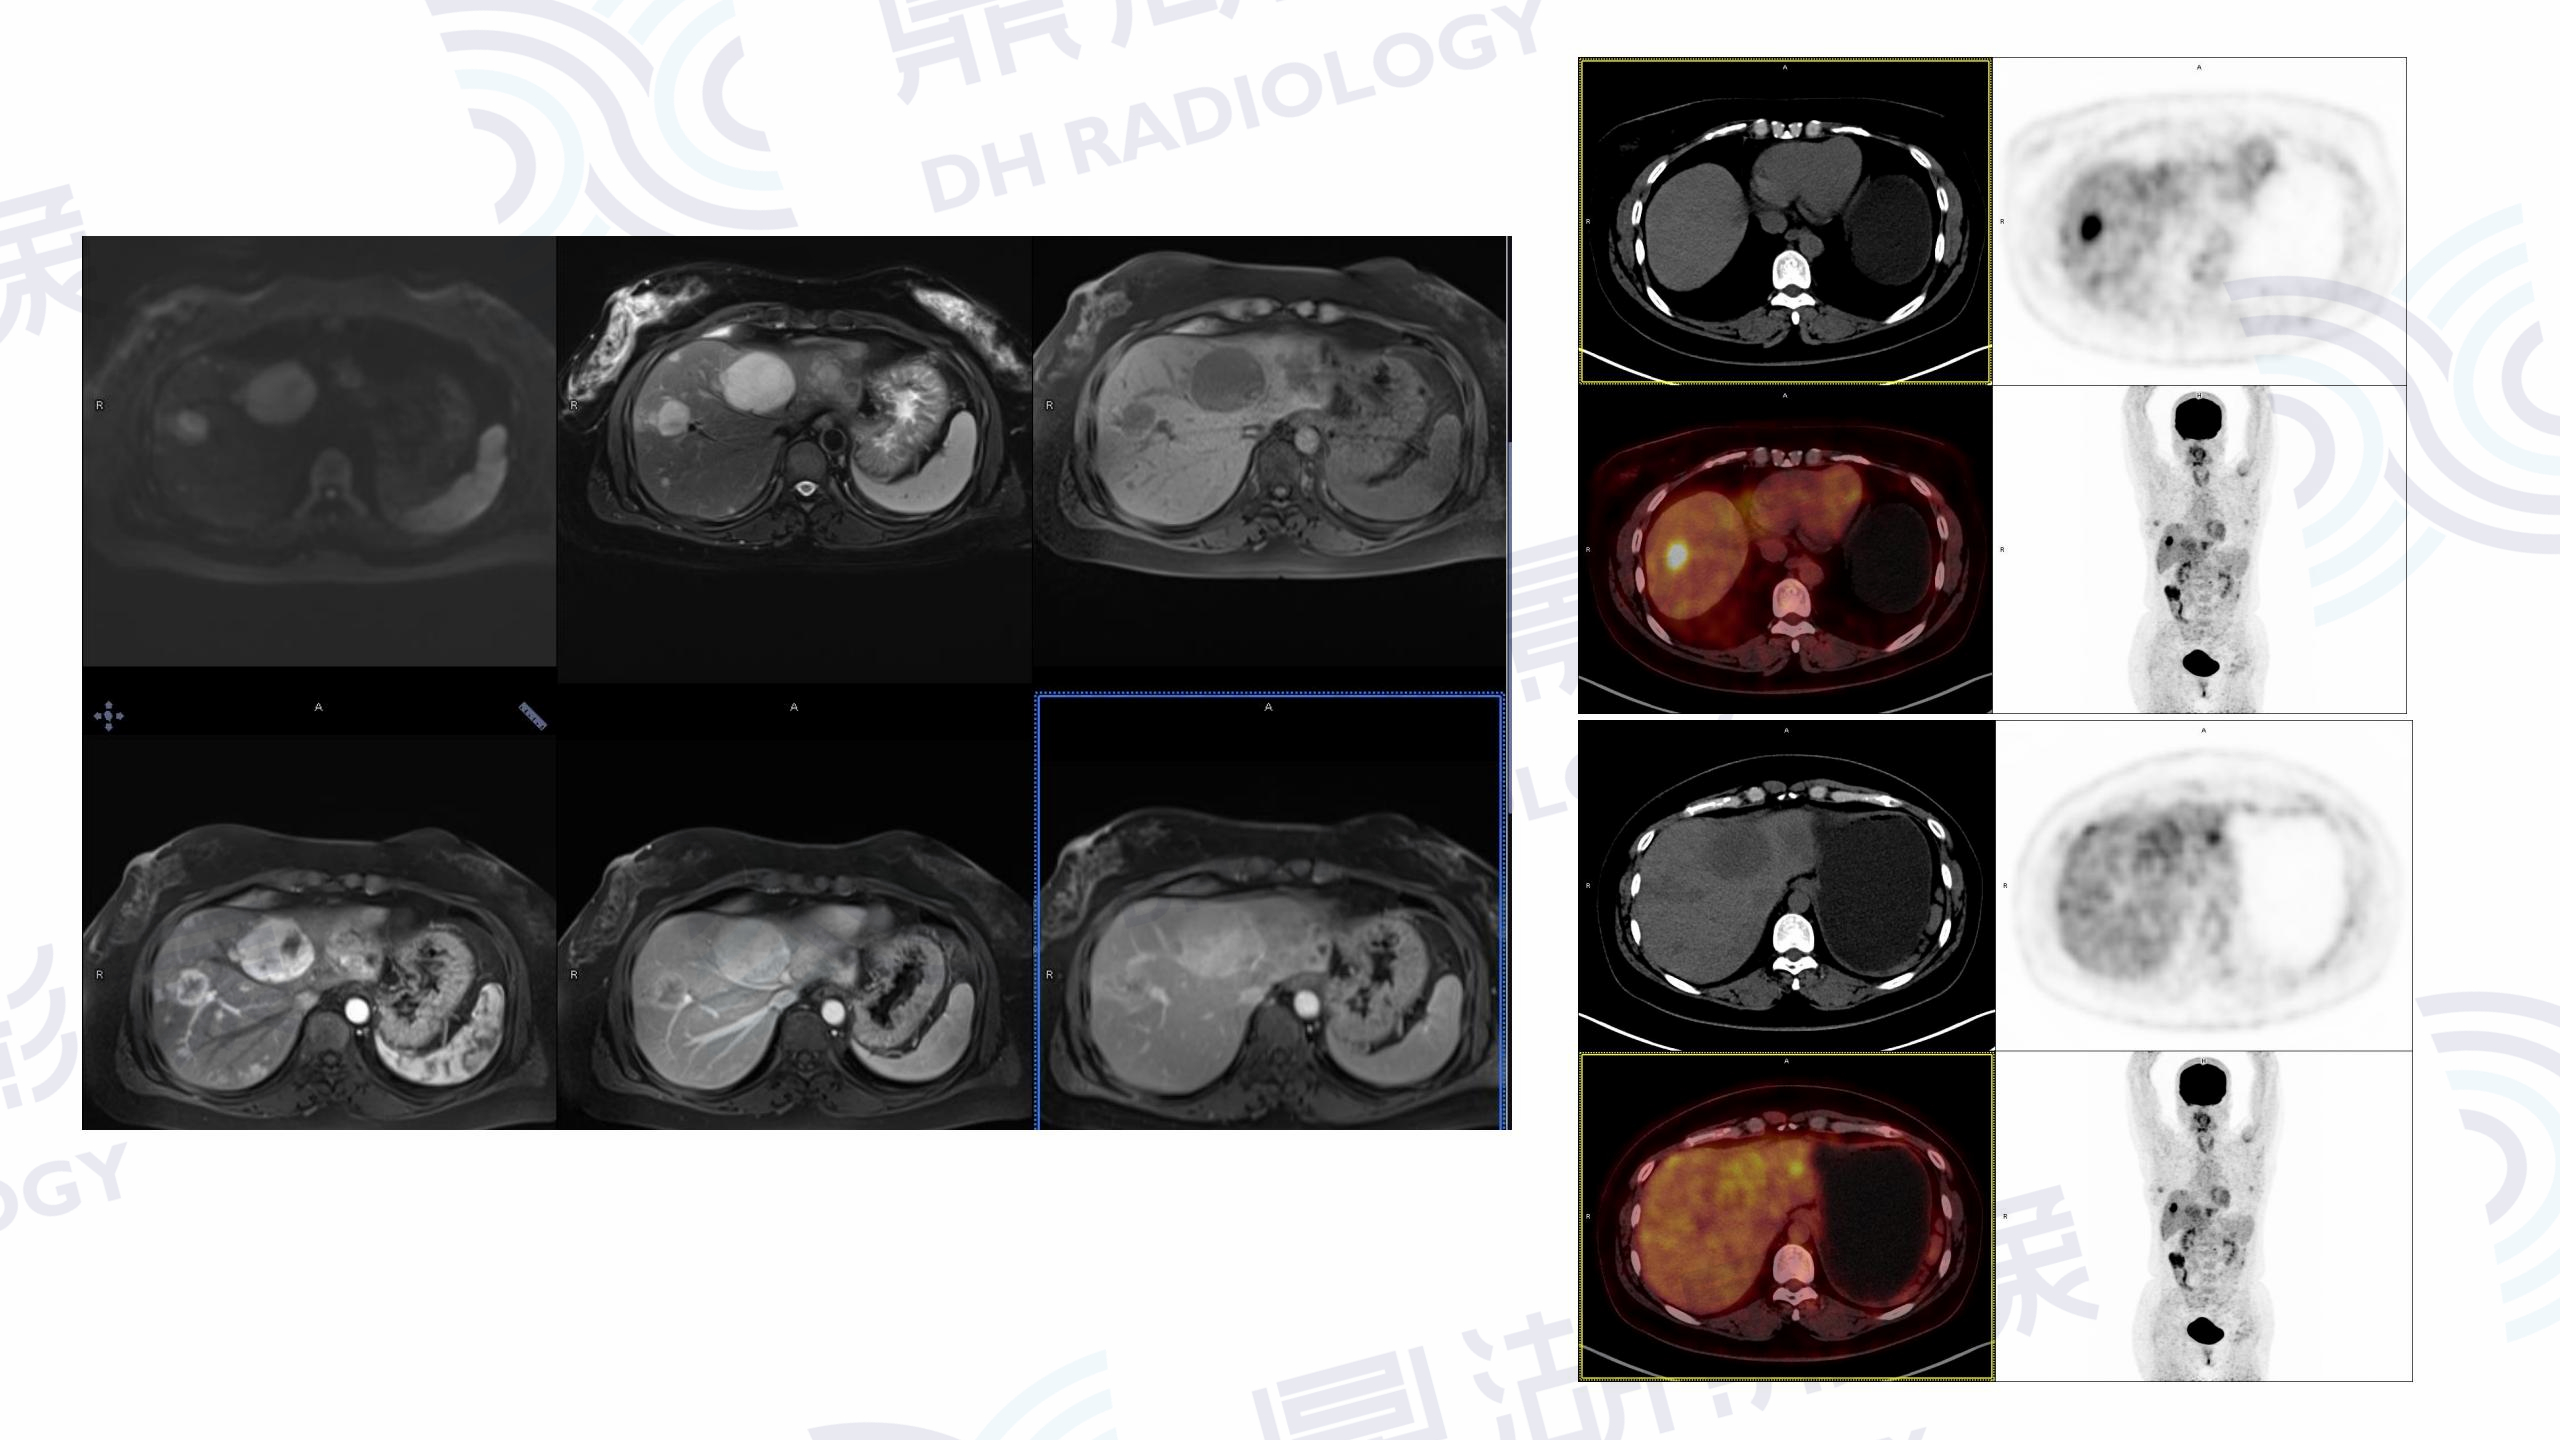

肝腺癌

腹部(消化、泌尿生殖)

PET

CT

性别:男

年龄:69

主诉:发现肝占位5天。

体检B超发现肝占位,肿瘤标志物CA199:65.51U/ml。数年前因胃部癌前病变行黏膜剥脱术,否认慢性乙肝病史,无发热表现。